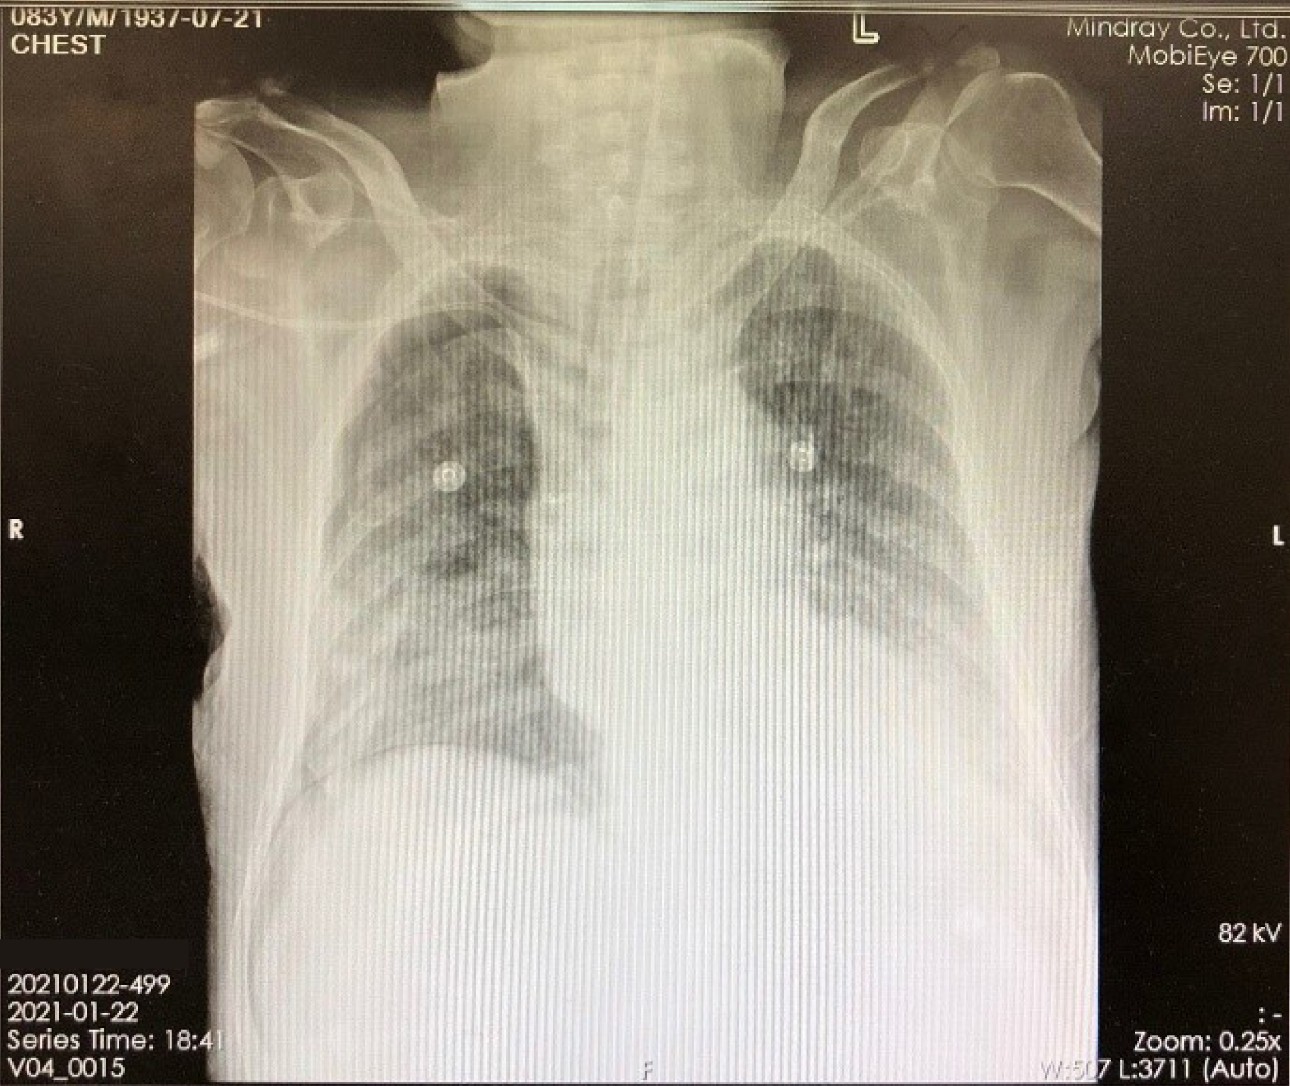

X-ray image (Figure 1) on January 22, 2021 showed about 30% compressing of the right lung, with multiple infections in both lungs. The CT examination results on January 25 also showed that the patient had infections in both lungs and a small amount of pleural effusion on the left side. On the same day, the aerobic culture + smear microscopy results of the lower respiratory tract specimen indicated the presence of Gram-negative bacilli and Gram-positive bacilli infections, and the results showed a large amount (>30/OIF).

Figure 1. Patient X-ray image